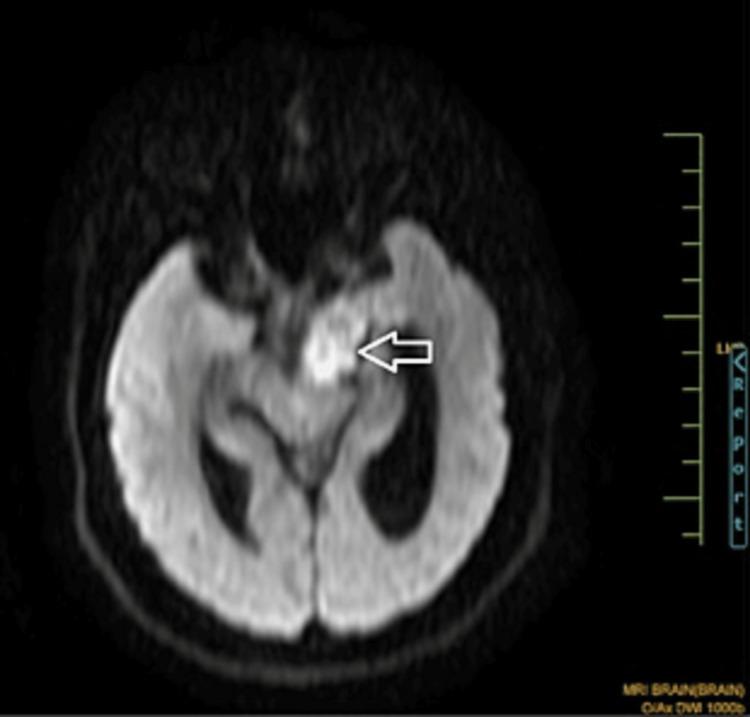

Magnetic Resonance Imaging Findings in a Rare Case of a Ruptured Intracranial Dermoid Cyst.

Intracranial dermoid cysts are rare, benign, congenital, and slow-growing cystic lesions. They contain mature squamous epithelium, apocrine, eccrine, sebaceous glands, and ectodermal structures. The rupture of intracranial dermoid cysts is a rare event and can cause life-threatening conditions.

颅内皮样囊肿是罕见的、良性的、先天性的、生长缓慢的囊性病变。它们包含成熟的鳞状上皮、顶泌汗腺、小汗腺、皮脂腺和外胚层结构。颅内皮样囊肿破裂是罕见事件,可导致危及生命的情况。